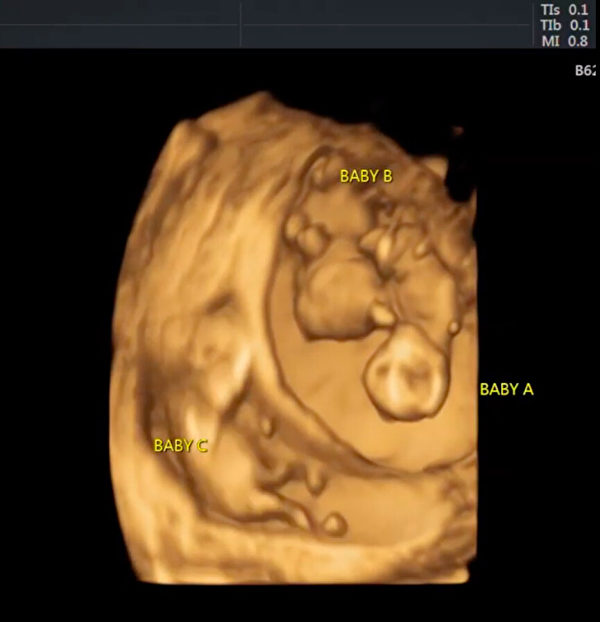

这种现象在医学上又称为异期复孕(superfetation),即妇女在怀孕后继续排卵时,就会发生这种现象。米歇尔的情况是,婴儿A和B是双胞胎,而婴儿C是在六天前怀孕的。

美国一对年轻的夫妇大概一年前获悉他们可能无法正常生育,然而令人惊喜的是,他们现在正期待着三个宝宝的陆续降生。(Dee & T Plus Three提供)

米歇尔于9月21日发布了为期12周的扫描图像,并解释说:“去年我的医生告诉我,我将无法生孩子,需要进行手术。但是上帝却拒绝了,并给了我们三个健康的婴儿和一个完全健康的母亲!”